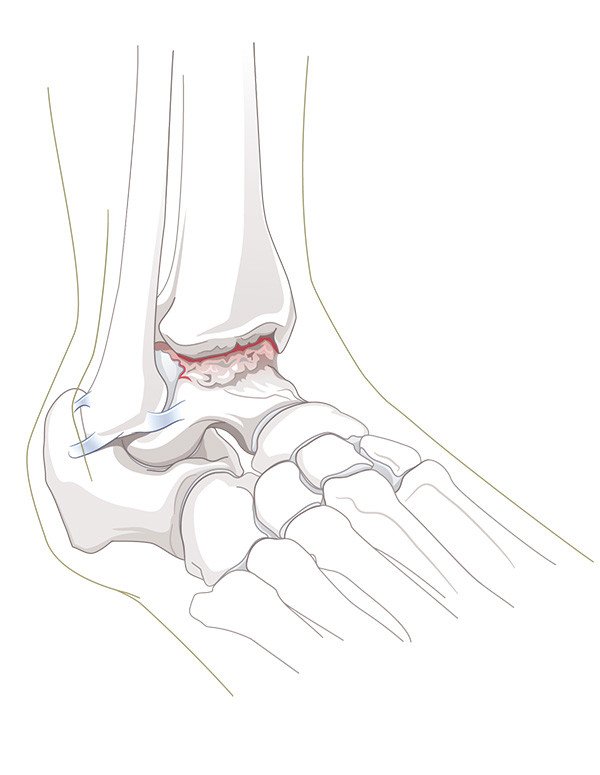

Das obere Sprunggelenk bildet die bewegliche Verbindung zwischen dem Unterschenkel (Schienbein und Wadenbein) und dem Sprungbein (Talus). Die Beweglichkeit des Rückfusses ist aber nicht nur durch dieses eine Gelenk gegeben, sondern durch die Summe eines komplexen Zusammenspiels sämtlicher Rückfussgelenke. Die zunehmende Abnützung des Gelenkknorpels, als Folge eines Unfalls oder im Rahmen einer entzündlichen Gelenkerkrankung, führt zur Arthrose im betroffenen Gelenk. Schmerzen und Bewegungseinschränkung sind die Folgen.

Bei schwerer Arthrose kommt in der Regel die Versorgung durch ein Kunstgelenk oder die Versteifungsoperation infrage. Beide Operationstechniken haben ihre Vor- und Nachteile. Faktoren wie das Ausmass der Arthrose, Fehlstellung und Knochenqualität spielen ebenso eine Rolle, wie Alter, Beruf und Freizeitaktivitäten.